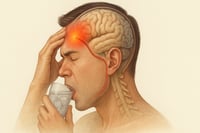

Beber algo muy frío o comer helado puede provocar una molestia repentina conocida como brain freeze o cerebro congelado una sensación que muchas personas…